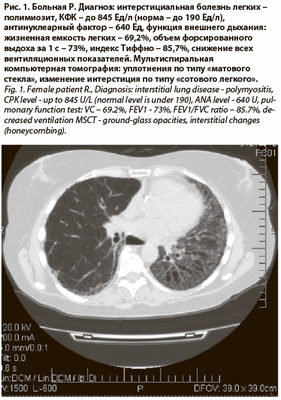

Поражение легких при антисинтетазном синдроме представлено прежде всего интерстициальным воспалением в виде МСКТ-паттерна «матового стекла» и тракционных бронхоэктазов (рис. 1) [5].